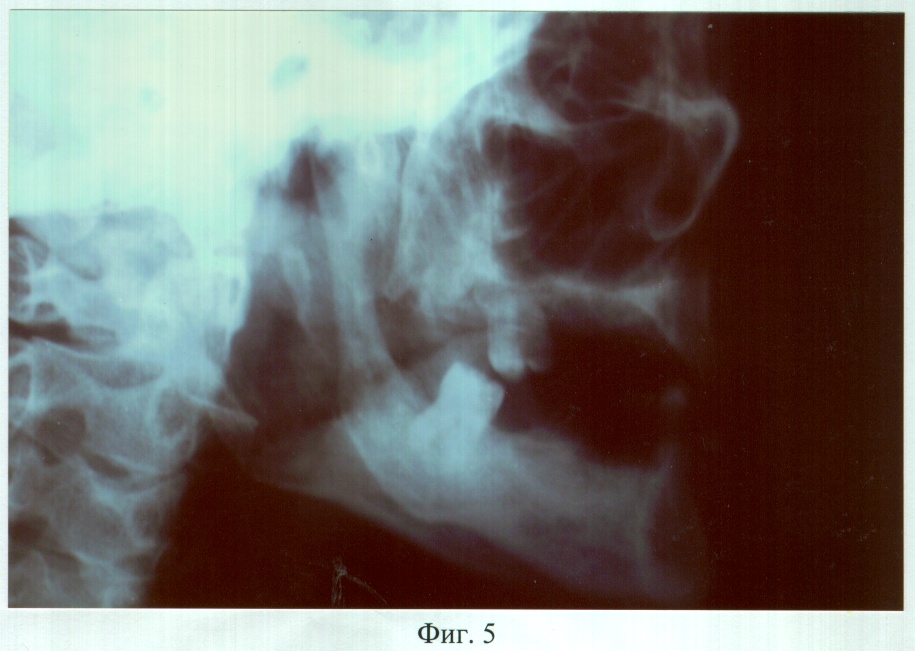

На фиг.5 – рентгенограмма больного М. до ортопедического лечения (левая латеральная проекция).

Пример 1. Больной М., 52 лет, обратился в клинику ортопедической стоматологии с жалобами на наличие дефекта твердого и мягкого неба, невозможность пережевывания пищи и попадание ее в полость носа, невнятность, гнусавость речи.

Из анамнеза: 4 года назад огнестрельное ранение, в результате которого образовался дефект твердого и мягкого неба, альвеолярного отростка правой верхней челюсти, фронтальной и правой дистальной части альвеолярного отростка нижней челюсти, верхней и нижней губы справа. Неоднократные попытки хирургической реконструкции дефекта твердого и мягкого неба не привели к желаемому результату. С целью восстановления нарушенных функций и устранения эстетических недостатков дважды были попытки изготовить зубочелюстной протез из акриловой пластмассы, эффекта не наступило.

Объективно: нарушение конфигурации лица за счет правосторонней рубцовой деформации и западения мягких тканей верхней и нижней губы, крыла носа. В проекции отсутствующих 18, 17, 16, 15, 14, 13, 12, 11; 46, 45, 44, 43, 42, 41, 31 зубов определялись аркообразные дефекты альвеолярных отростков. Ротовая полость сообщалась с носовой и носоглоткой посредством дефекта переднего и заднего отделов твердого и отсутствия мягкого неба, с сохранением 1/2 части небного отростка левой верхней челюсти. Слизистая оболочка преддверия, собственно ротовой полости, покрывающая костный изъян и ткани языка, рубцово изменены. Зубная формула: 22, 28, 32, 33, 34, 35, 47.

DS: Травматический дефект (субтотальный твердого, тотальный мягкого неба, аркообразные альвеолярного отростка правой верхней, альвеолярной части нижней челюстей в проекции отсутствующих 18, 17, 16, 15, 14, 13, 12, 11, 31, 41, 42, 43, 44, 45, 46 зубов), рубцовая деформация мягких тканей ротовой полости. Частичная вторичная верхнечелюстная и нижнечелюстная адентия II класса по Кенеди.